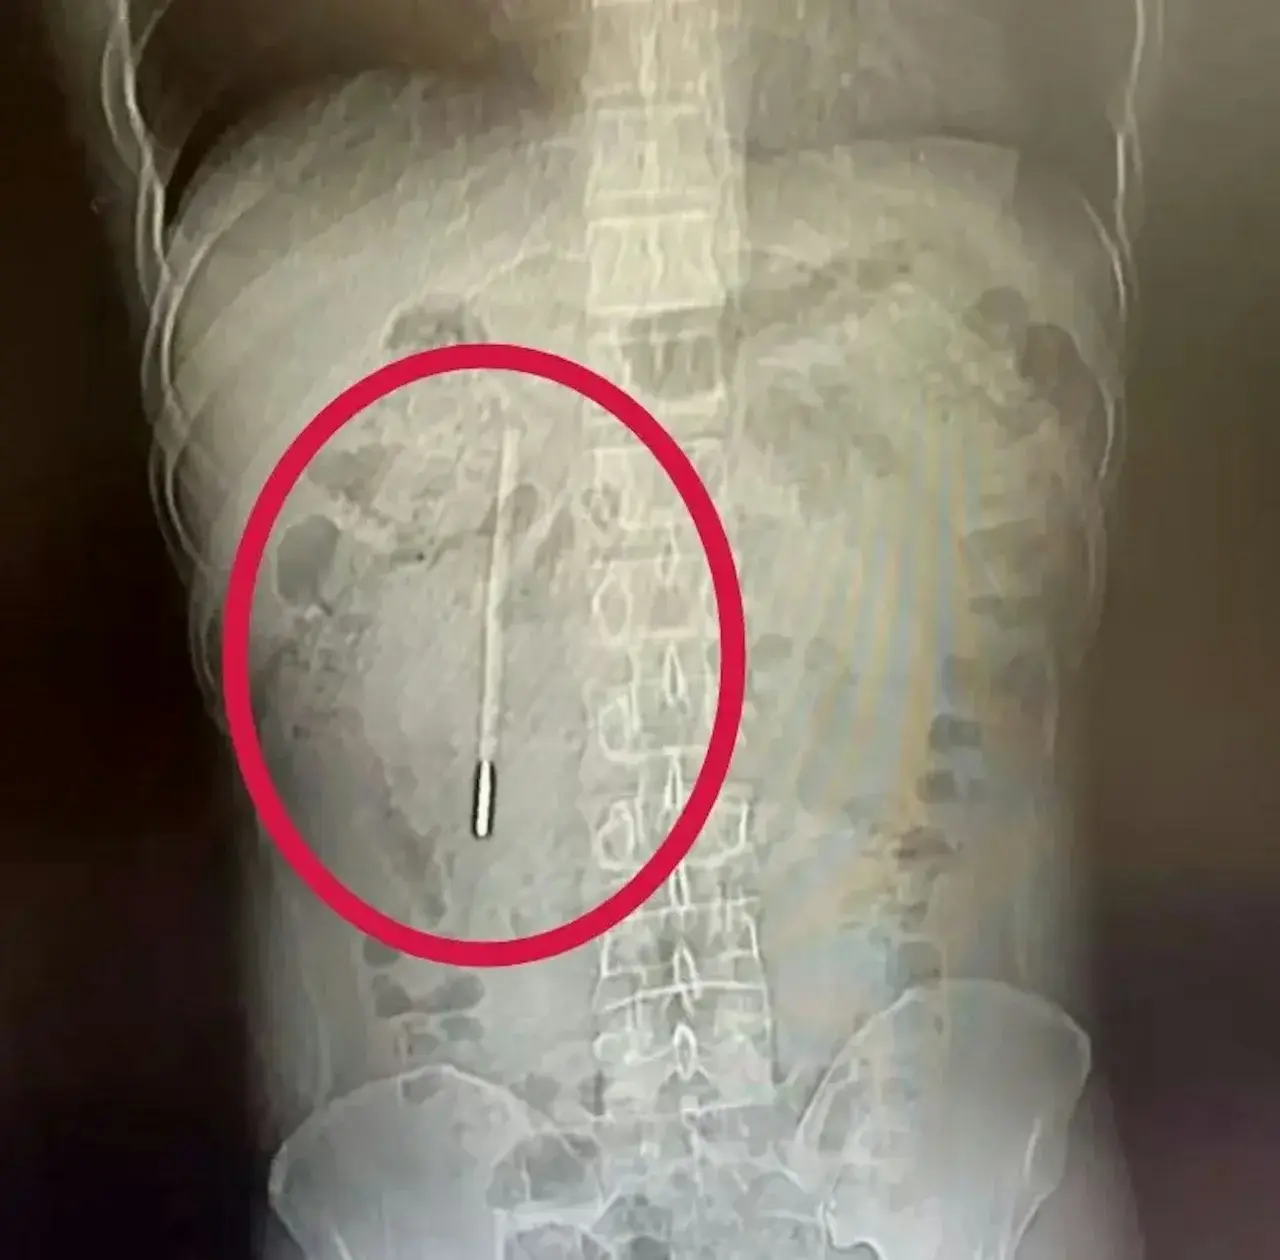

เปิดภาพ X-ray พบสิ่งแปลกปลอมในลำไส้เล็ก

จากการตรวจด้วยการสแกนคอมพิวเตอร์ (CT Scan) ทีมแพทย์พบวัตถุรูปร่างเรียวยาวคล้ายแท่งแก้ว ติดค้างอยู่ในบริเวณ ลำไส้เล็กส่วนดูโอดีนัม (Duodenum) ซึ่งเป็นจุดที่อันตรายเนื่องจากอยู่ใกล้กับท่อน้ำดีและตับอ่อน เมื่อซักประวัติอย่างละเอียด คนไข้สารภาพว่าเขาได้ "เผลอกลืนปรอทวัดไข้" ลงไปตั้งแต่อายุ 12 ปี แต่ด้วยความกลัวความผิดจึงไม่ได้บอกผู้ปกครอง และเห็นว่าไม่มีอาการเจ็บปวดใดๆ ในช่วงแรก จึงปล่อยทิ้งไว้นานถึง 20 ปี